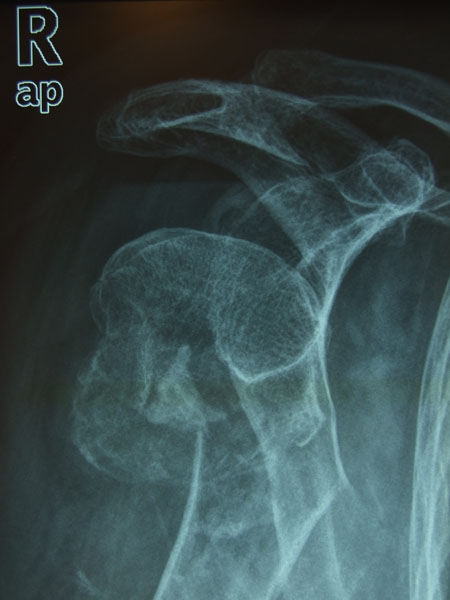

Fractura impactada de húmero .

Fractura de húmero, intensa desviación de fragmentos

Fractura de húmero.

Fractura compleja de húmero.

Fractura subcapital de húmero.